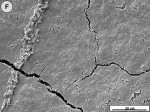

When the tooth slices with the ex vivo-grown salivary biofilm were examined under the scanning electron microscope, they were colonized by luxuriant biofilm covering the entire surface (Figure 2A, Figure 2B, Figure 2C). The biofilms appeared to be several micrometers thick. The predominant morphotypes in the biofilms were fusiform bacteria and cocci. Several regions showed co-aggregation between the two morphotypes, which is a phenomenon of mutual dependence for nutrition and growth. The salivary-derived biofilm showed characteristics typical of a naturally occurring in vivo biofilm in the mouth. The standard jet tip treatment for 3 seconds on the tooth slices with ex vivo-grown biofilm showed extensive areas of biofilm removal in comparison with the untreated control slices (Figure 2D, Figure 2E, Figure 2F). The standard jet removed 99.99% of the salivary biofilms. The orthodontic tip treatment for 3 seconds on the tooth slices appeared to clear very extensive areas of ex vivo-grown salivary biofilm (Figure 3A andFigure 3B). Biofilm removal was observed both at the crown surface and below the cementoenamel junction. The percentage of biofilm removed by the orthodontic tip was 99.84%. Observation with the naked eye indicated that treatment of in vivo biofilm with the orthodontic tip removed significant amounts of this calcified biofilm. This was evident in SEMs, which showed the presence of clearance marks (Figure 3C) caused by the bristles associated with this tip.

Comparing dental biofilm against the whole spectrum of biofilm studied by biofilm engineers, dental biofilm’s susceptibility to removal by shear forces fits into a logical pattern. Microbial biofilms have been shown to vary the cross-linking of the component polymers of their matrices to develop a tensile strength appropriate for their retention on surfaces in the ecosystem in which they operate. Various degrees of mineralization of biofilms make them much more resistant to removal by shear forces. In the oral ecosystem, mineralization takes the form of calcification, and the deeper layers of the biofilm used in this study were, in fact, calcified to the extent that they had tensile strengths approaching that of the enamel of the tooth. For this reason, the authors distinguished between the removal of less calcified ex vivo salivary biofilm and the removal of calcified biofilm that had formed over a long period on the patient’s teeth in vivo.

This study demonstrated microscopically that the hydraulic forces produced by a dental water jet with 1,200 pulsations per minute on medium pressure (˜70 psi) (Water Pik, Inc) can significantly remove biofilm from tooth surfaces above and below the cementoenamel junction in vitro. A standard jet tip can remove 99.99% of ex vivo-grown biofilm with 3 seconds of use. An orthodontic tip can remove 99.84% of ex vivo-grown biofilm with 3 seconds of use. And, an orthodontic tip can remove in vivo-grown biofilm significantly with 3 seconds of use, as observed by the naked eye and SEM.